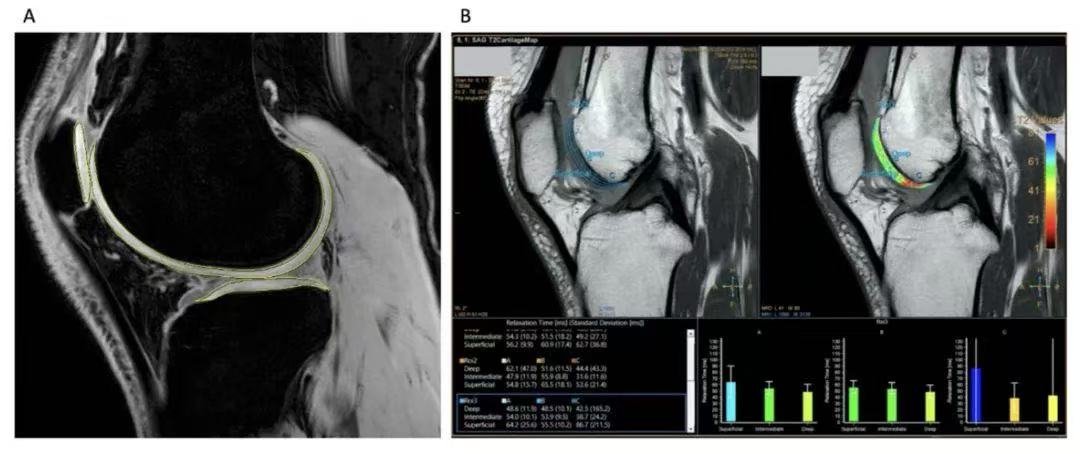

- Verified Regeneration: MRI examinations confirmed reduced knee edema and an increase in articular cartilage volume.

- Comprehensive Exams: MRI, X-ray, KL-grading.

- MRI & WOMAC score progress assessments.

| MRI Cartilage Score | 40 | 60 | ↑ 50% |